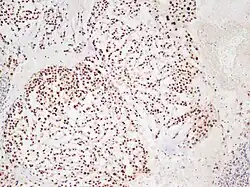

Chordoma showing nuclear staining for brachyury using immunohistochemistry.

There are three histological variants of chordoma: conventional,[14] chondroid and dedifferentiated.

• The histological appearance of classical chordoma is of a lobulated tumor composed of groups of cells separated by fibrous septa. The cells have small round nuclei and abundant vacuolated cytoplasm, sometimes described as "physaliferous" because of their cytoplasmic vacuoles, and their resemblance to the physalis plant.